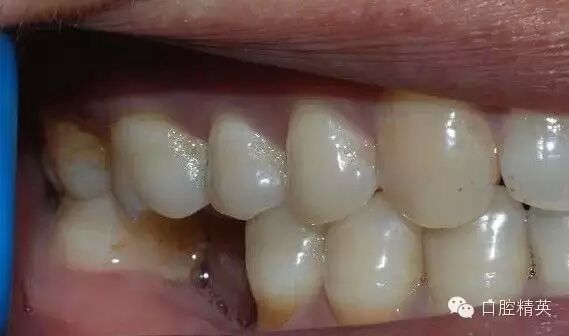

46缺失,不考慮種植牙,45、47做基牙,固定烤瓷橋修復(fù);這是口內(nèi)的情況

咬合時(shí)的情況